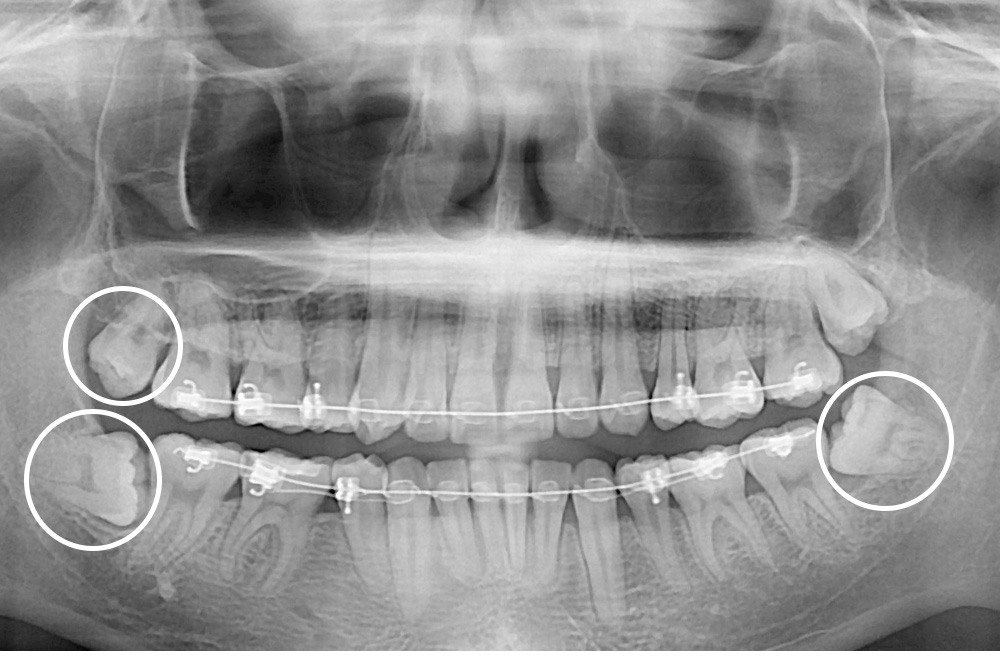

[사랑니] 매복 사랑니 발치

치료전 : 2020-07-13